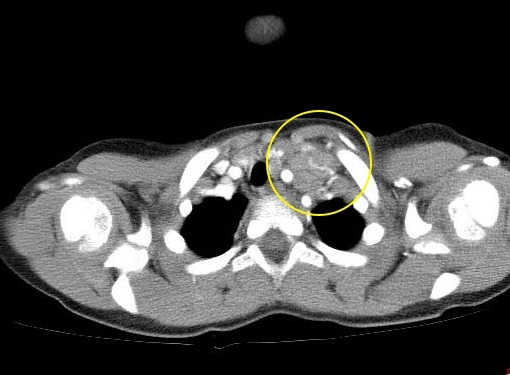

Рис. 3. Поражение внутригрудных лимфатических узлов при лимфоме Ходжкина